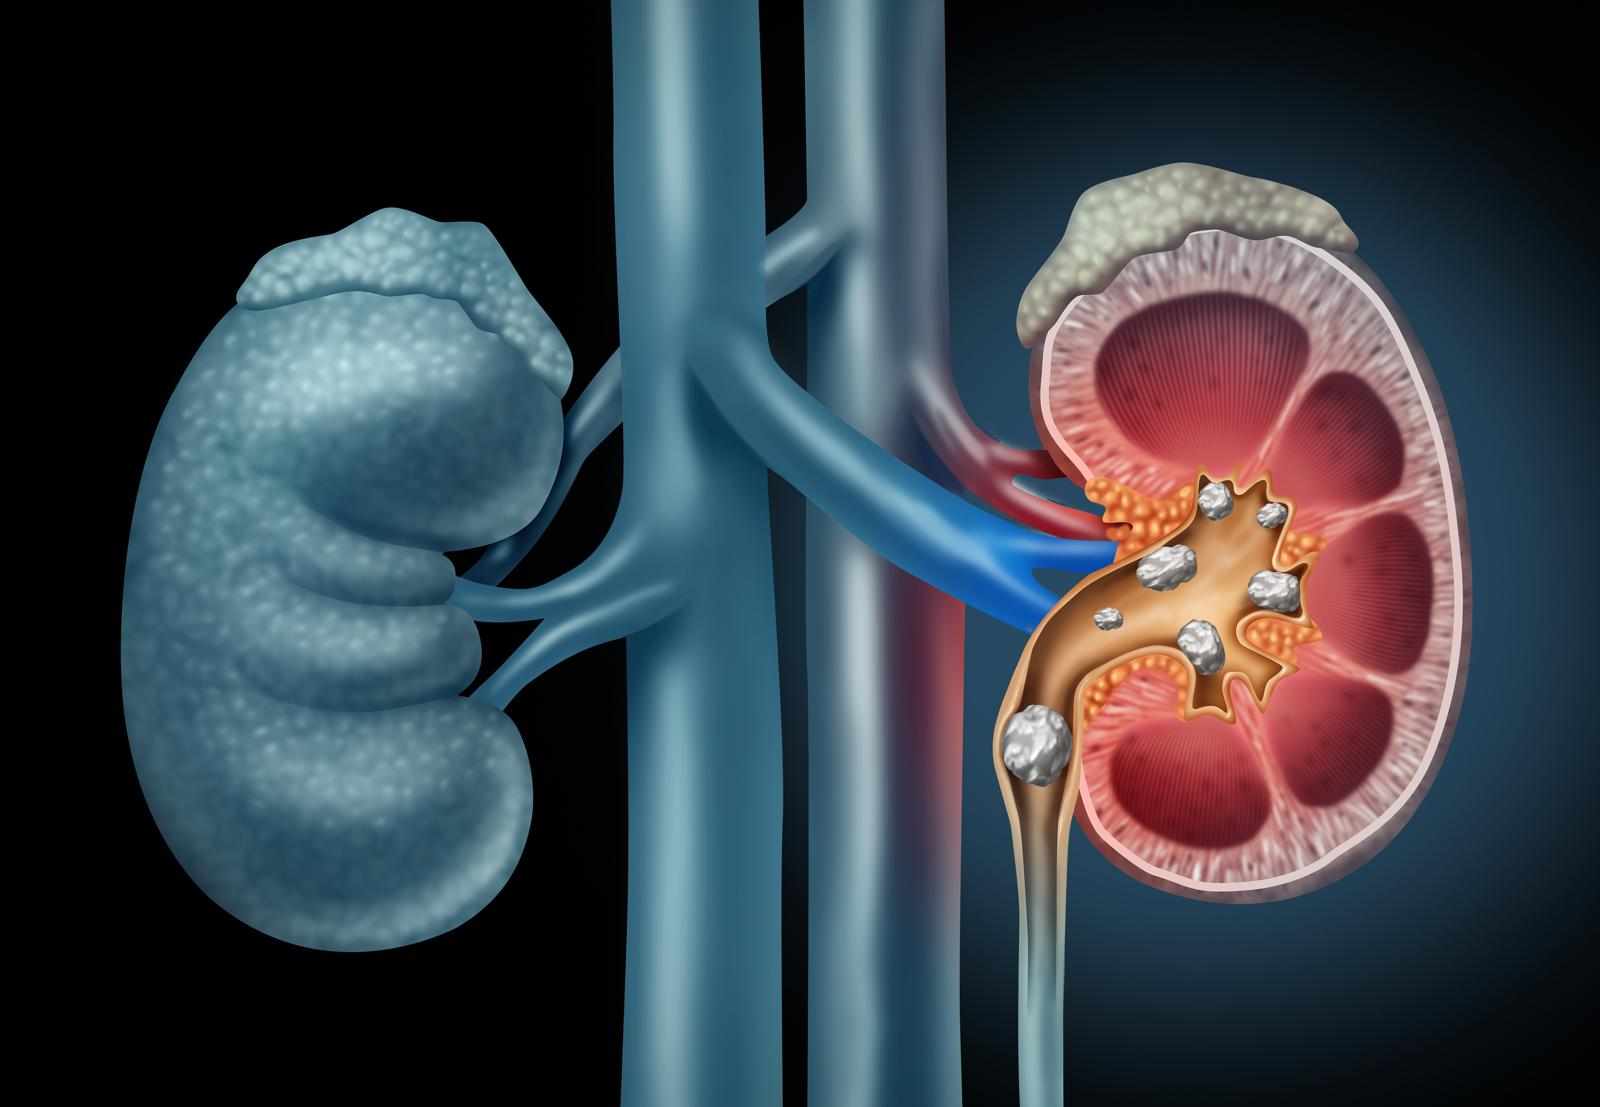

In addition to autoimmune disorders, homeopathy has also been shown to be effective for managing conditions like gout and high uric acid levels, which often accompany autoimmune diseases. Homeo treatment for uric acid focuses on addressing the underlying causes of the condition, such as poor metabolism and dietary factors, while also reducing inflammation and pain associated with uric acid buildup. By promoting better kidney function and optimizing the body’s elimination processes, homeopathy can help manage uric acid levels without the side effects of traditional medications.